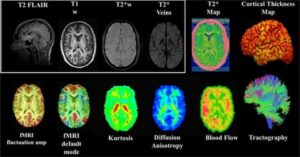

The study is testing biomarkers, or measurable signals in blood and/or imaging, that may reveal how the brain responds to concussions, repeated head impacts, and other health risk factors. These include advanced scans like MRI and PET (positron emission tomography), as well as blood-based markers that show inflammation or damage long before symptoms appear.